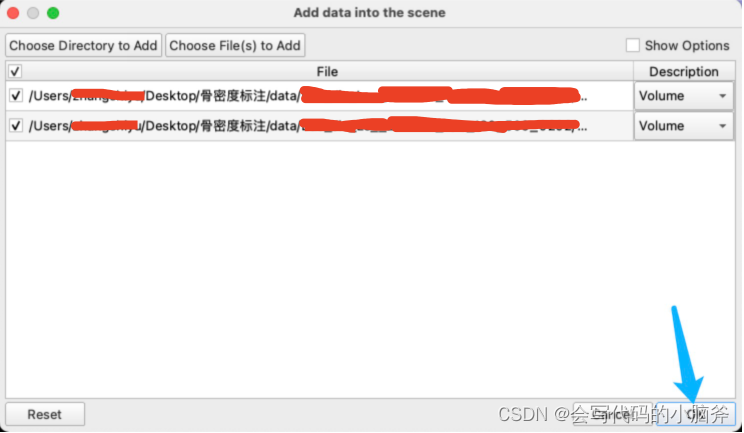

- 导入数据: